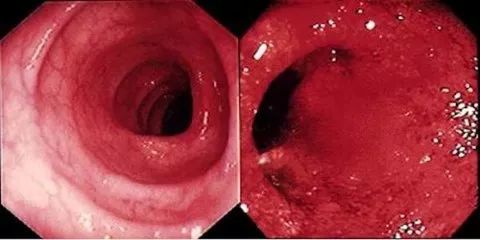

正常肠道与炎症肠道

而另一个实验则针对29名克罗恩病(同样是一种肠道炎症疾病)患者 。 同样是每两周服用一次活猪鞭虫卵 , 实验持续24周 。

实验结束时 , 80%的患者称自身症状减轻 , 72%患者的症状已基本得到缓解 。 这些结果都远远超过了安慰剂组的治疗效果 , 且未出现任何副作用 。